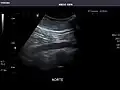

Kidneys: Right and left kidneys measure 11.5 cm and 12 cm in length respectively. No hydronephrosis. Small left lower pole kidney cyst.

Right kidney -